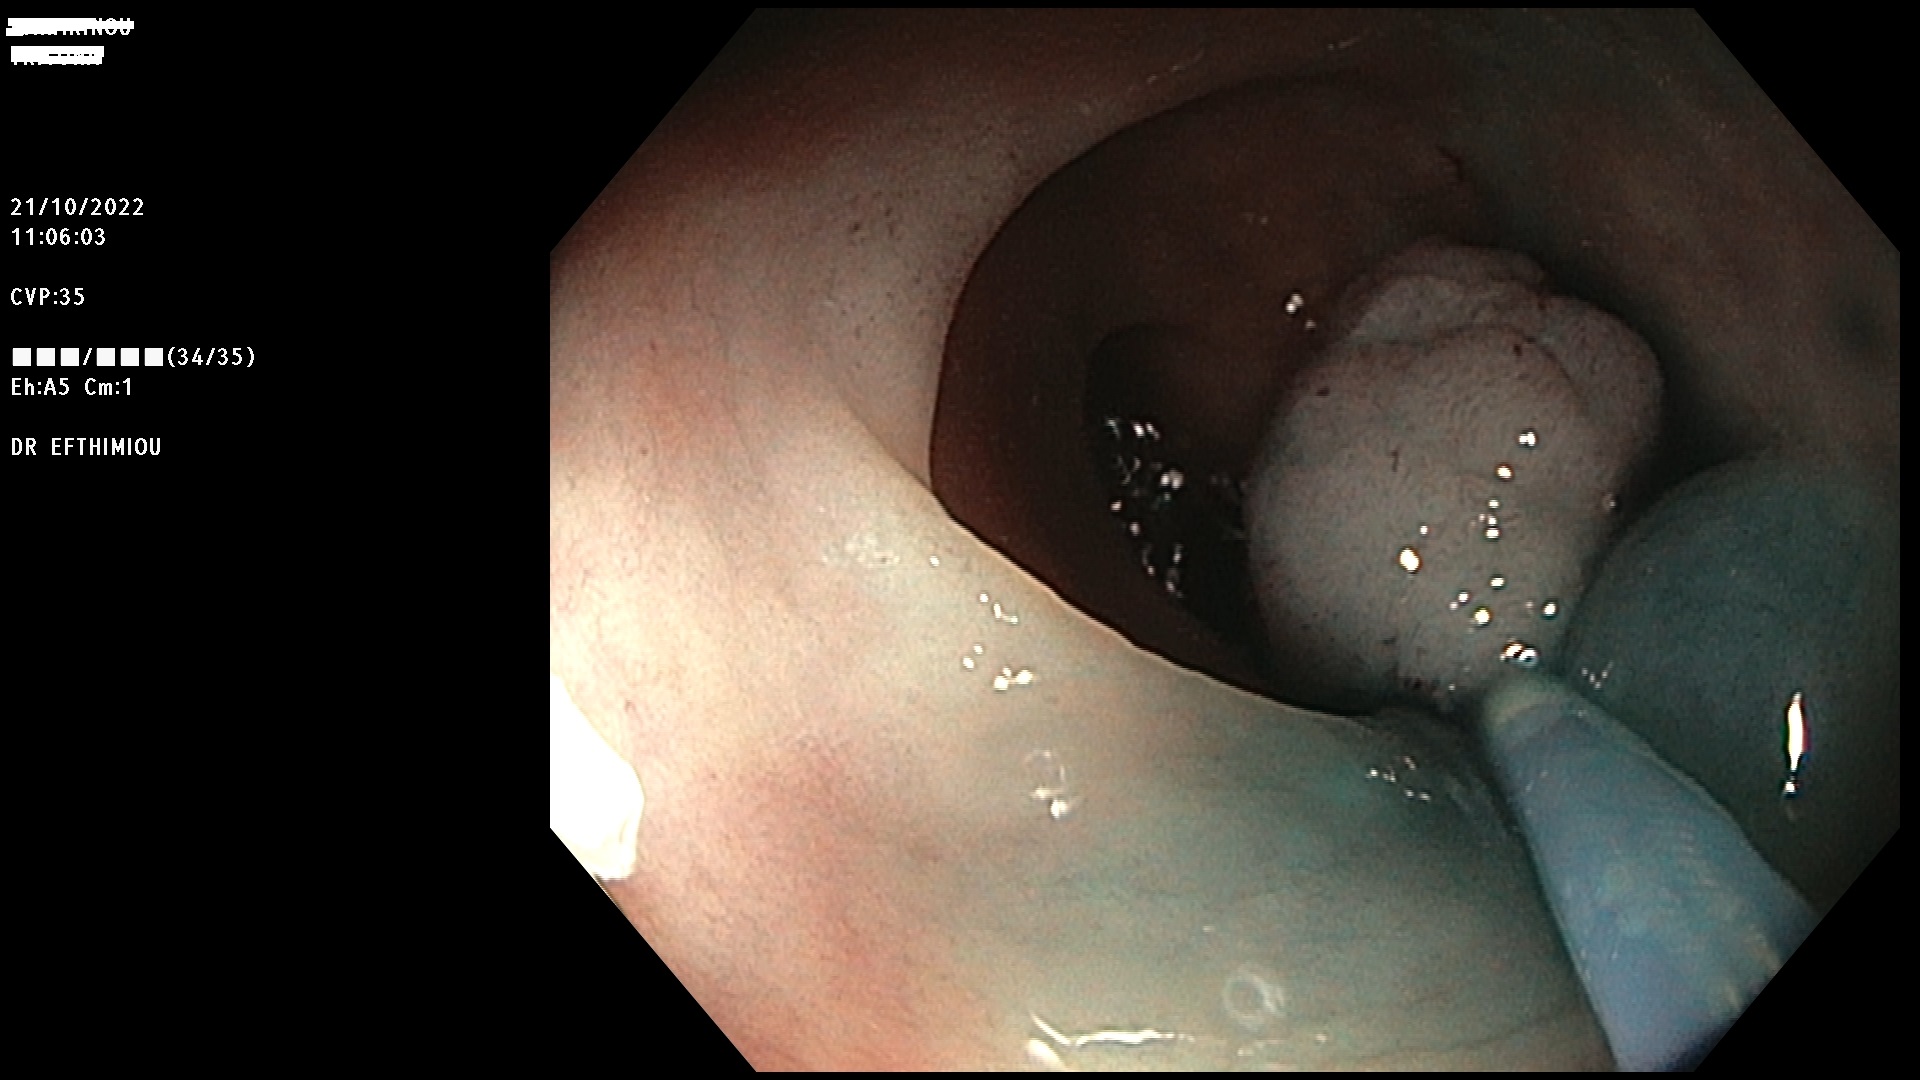

Η επέμβαση γίνεται κατά τη διάρκεια της κολονοσκόπησης με τη χρήση

διαφόρων εργαλείων (λαβίδες, βελόνες υποβλεννογόνιας έγχυσης, βρόχοι

διαθερμίας, ψυχροί βρόχοι, endoloops, κ.ά.) ανάλογα με το μέγεθος, τη

μορφολογία και την εντόπιση του πολύποδα (Εικόνες 1-3). Ο ασθενής

βρίσκεται σε ήπια καταστολή («μέθη») και δεν αισθάνεται καθόλου πόνο.